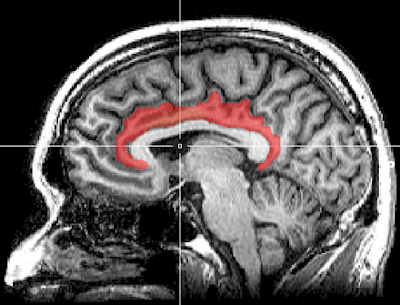

الصورة تشير إلى موضع التلم داخل الفص الجداري. مصدر الصورة: جامعة تكساس

”بأمكانك اعتبار التلم داخل الفص الجداري intraparietal sulcus في الدماغ أنه يحتوي على قرصي تغيير محطات إذاعية في جهاز الراديو: أحدهما يضبط التركيز والآخر يضبط الفلترة،“ قال ريتز. "في دراستنا، منطقة القشرة الحزامية الأمامية [5] في الدماغ تتبع ما يحدث مع النقاط التي تتحرك في دوامة سريعة. عندما تدرك القشرة الحزامية الأمامية، على سبيل المثال، أن الحركة تجعل المهمة أكثر صعوبة، فإنها توجه التلم داخل الجداري لضبط قرص الفلترة لخفض حساسيته للحركة.